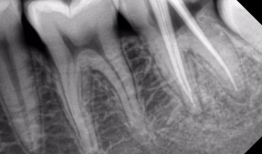

根管治疗视频,从视频学习根管治疗技巧与流程

最近是不是牙齿疼得你坐立不安,连笑容都变得苦涩了呢?别担心,今天就来给你揭秘一下那个听起来有点吓人的根管治疗,让你对这个过程有个...